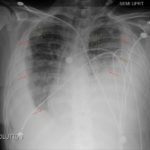

Upright frontal radiograph of the chest demonstrated large pleural effusion on the left and moderate pleural effusion on the right as shown by the visible menisci on both sides (red arrows) with diffuse bilateral nodular densities (yellow dotted lines), consistent with septic pulmonary emboli. Computed tomography (CT) of the chest demonstrated multiple scattered lung nodules bilaterally containing internal foci of air cavitation (green dotted lines).